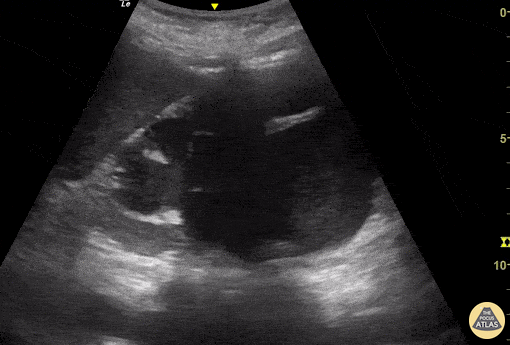

Objectif

Recherche d'OAP, de pneumopathies ou de surcharge interstitielle.

Points clés

- Identification des lignes A (physiologiques) vs lignes B (pathologiques si > 3 par espace intercostal).

- Balayage : 6–8 zones (ou BLUE points).

- Compréhension du protocole BLUE pour le diagnostic différentiel de la dyspnée.

- Repérage des condensations sous-pleurales.